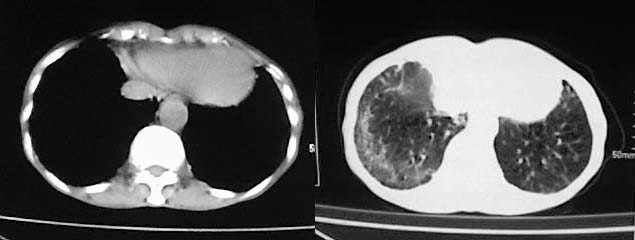

以下是引用有风的日子在2008-5-2 12:13:00的发言:[br][emb10][br][br]肺ca?有病理支持吗?[br][br]我看更象是肺tb并支扩、间质性肺炎。最好拿个病理结果来,不然这点影像资料诊断肺ca是难以服人的![br][br]至于主动脉瘤的诊断问题,国外认为≥4.0cm就可诊断了,国内对此诊断标准更为严格。患者升主动脉明显增粗,即>4cm。你诊断个升主动脉扩张并不为过!

以下是引用zjzjr在2008-5-2 14:39:00的发言:[br]支持双侧继发型肺结核,左侧胸膜肥厚,慢性支气管炎伴间质纤维化.